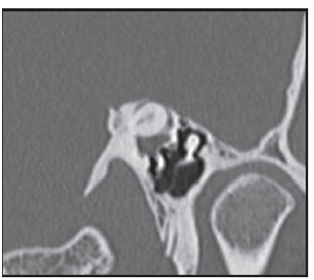

Figure 4b Rendering reconstruction volume highlighting the defect adjacent to the upper wall of CSCS, shown by arrows 4c rojas. Figure bone surface. MPR oblique parallel to the plane of the CSCS which highlights the ósea.VCL wall dehiscence. With the clinical suspicion of DCSS syndrome in left ear temporal bone CT is performed, with cuts of 0.5 mm, which confirms the clinical diagnosis.

Figure 4c MPR oblicuo paralelo al plano del CSCS donde destaca la dehiscencia de la pared ósea.